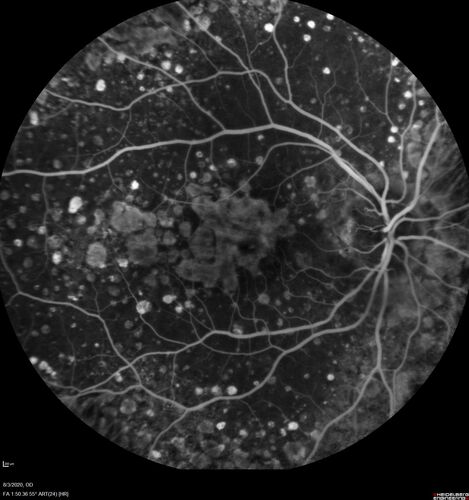

Dry AMD geographic atrophy and cystoid macular edema

79 year old vision is in for a checkup with no visual complaints in the left eye.  This is her better eye.  VA 20/200 OD, 20/50 OS.  3 years ago she had a CRVO in the left eye.  She is also diabetic for 20 years, has carotid insufficiency and anemia.  Left eye shows CME.  This was not treated and the vision improved to 20/40 over the next year although mild edema persisted.